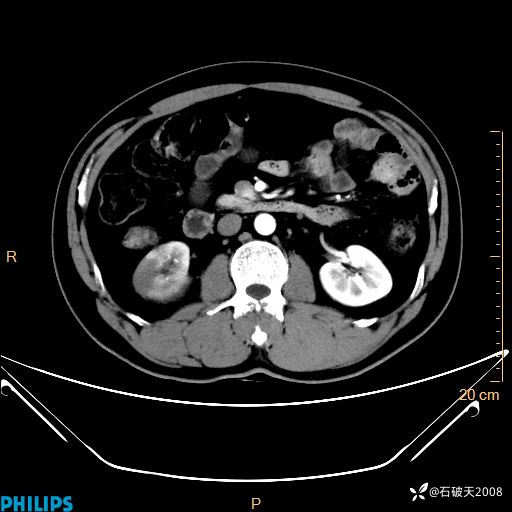

平扫轴位